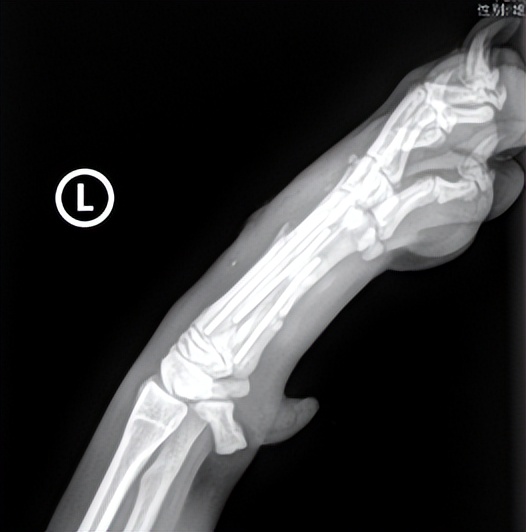

DR可见左掌2.3.4.5掌骨骨折。摔伤后前肢跛行,骨折中排除肱骨、桡尺骨骨折,也要小心掌骨、跖骨、趾骨骨折,评估伴发的四肢远端的韧带损伤,DR拍摄可以用于区分骨折或关节脱位或软组织损伤。

左掌2.3.4.5掌骨骨折

采用 外科手术治疗,克氏针进行内固定,术后再用玻璃纤维绷带进行外固定 ,限制活动,避免激烈运动,使用1-2周的抗生素和非甾体抗炎止痛药,术后观察外固定情况,在1、2、4、8周复查DR时,根据骨折愈合情况拆掉外固定。

术后1周后复查DR结果如下